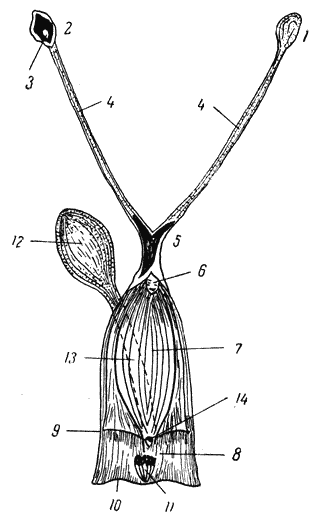

Сердце у собаки расположено на четыре седьмых своей величины в левой половине грудной полости и на три седьмых — в правой. Основание сердца находится на половине высоты грудной клетки. Задний край сердца в шестом межреберном промежутке спускается вниз и приближается к седьмому ребру. Верхушка сердца только на 1 см не доходит до дорсальной поверхности грудной кости. Задняя часть сердца покрыта краем левого легкого (рис. 1).

Рис. 1. Грудная клетка собаки